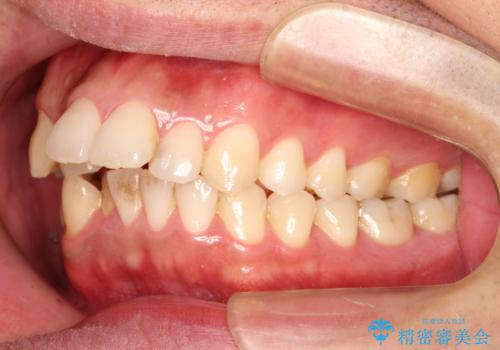

出っ歯の抜歯矯正 裏側ワイヤーによる目立たない矯正

- 出っ歯が気になるとのことで来院されました。

上顎の前から4番目の歯を両側、合計2本抜歯して矯正する計画としました。

目立たない装置がご希望でしたので、上下裏側ワイヤー装置を選択されました。